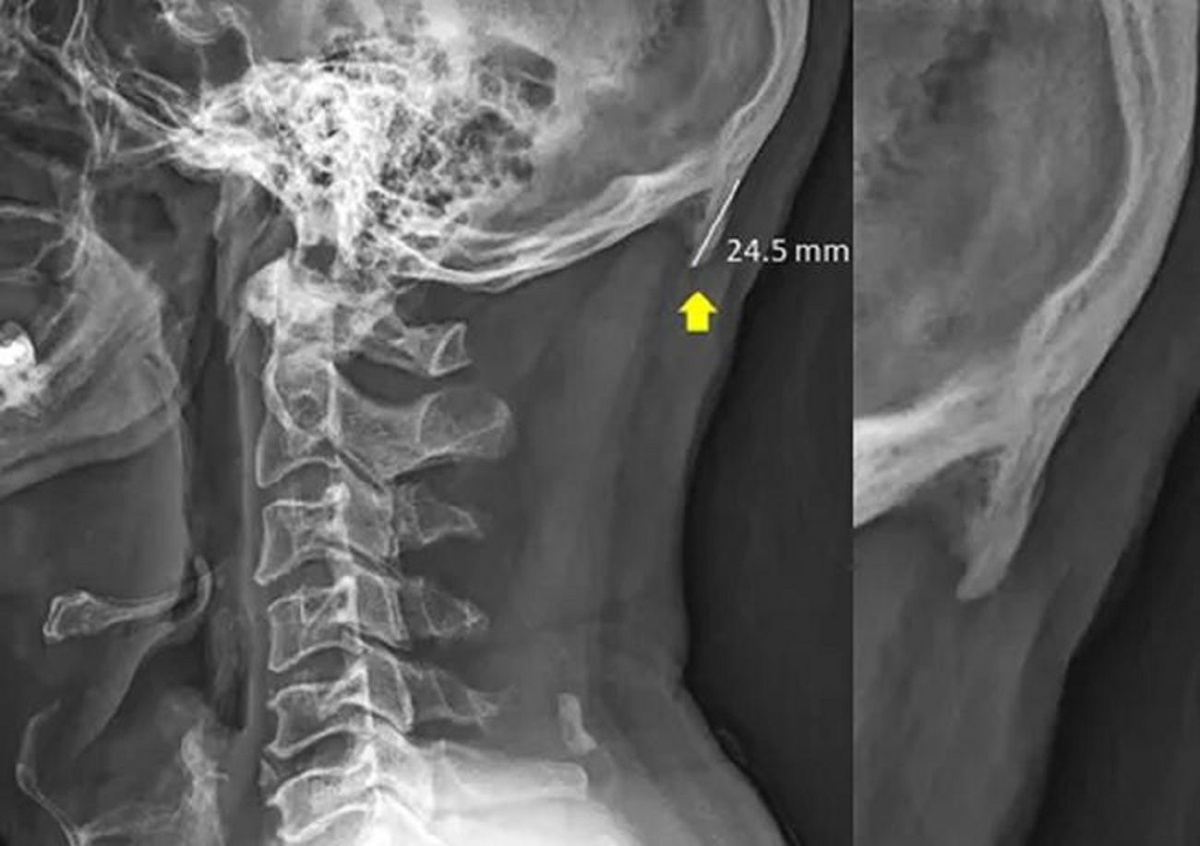

1. Практика показывает, что если вы добавите в название новостной или научной статьи слова «смартфон» или «айфон», то шансы на повышенное число прочтений заметно возрастут. При этом тема может быть совершенно не связана с данными гаджетами. Паре австралийских учёных оказалось достаточно упомянуть смартфоны в качестве возможной причины образования затылочного выроста у обследованных ими молодых людей, и это обеспечило внимание СМИ к их работе:

Идея авторов была в том, что нарушение осанки у пользователей мобильных устройств приводит к адаптивным изменениям черепа. Весьма забавная гипотеза, если учесть, что когда-то затылки у древних людей были более вытянутые и заострённые, так как к ним крепились массивные челюстные мышцы, необходимые для жевания сырой пищи. Смартфоны приводят к деградации нашей молодёжи... ну, вы поняли.

Полтора года спустя, однако, авторы опубликовали новую версию статьи, исключив из неё упоминание телефонов. Они признались в том, что «их выборка может быть искажена, а также, что у одного из них есть конфликт интересов: он занимается хиропрактикой и предлагает услуги по исправлению осанки».